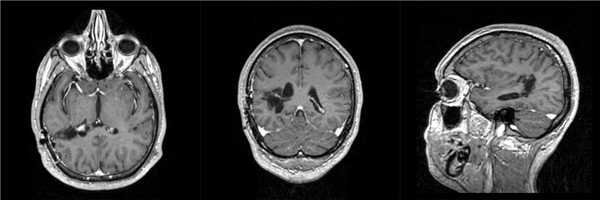

Пациентка 19 лет, впервые МРТ головного мозга выполнена 6 лет назад после перенесенного эпилептического приступа - выявлена внутримозговая опухоль левой височной доли. Лечение не проводилось. После первично-генерализованного эпиприступа вновь выполнена МРТ, выявившая значительное увеличение размеров опухоли.

Пациентке проведена операция - радикальное удаление опухоли. Гистологический диагноз - ганглиоглиома. При контрольной СКТ на 1 сутки после операции данных за послеоперационные осложнения или остатки опухоли не получено.

Больная выписана на 4 сутки после операции без неврологического дефицита.![]()